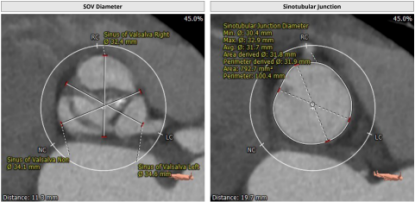

主动脉CT

本病例窦部情况可,瓣环周长24mm左右,判断使用VitaFlow24或VitaFlow27号瓣膜。